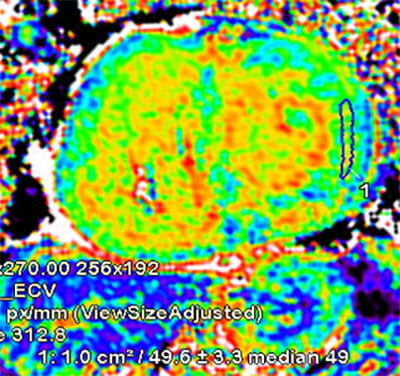

• High volume program with daily case averages of 10 CMR studies and 25-35 cardiac CTAs (50% coronary CTA, 30% structural, 20% other). Broad case complexity, including CAD, structural heart pathologies, congenital heart disease,  and implantable devices. Routine use of cutting edge technology, including T1/ECV mapping, quantitative perfusion, free-breathing CMR exam, artificial intelligence based CT analyses, CT-FFR, structural planning and simulation.